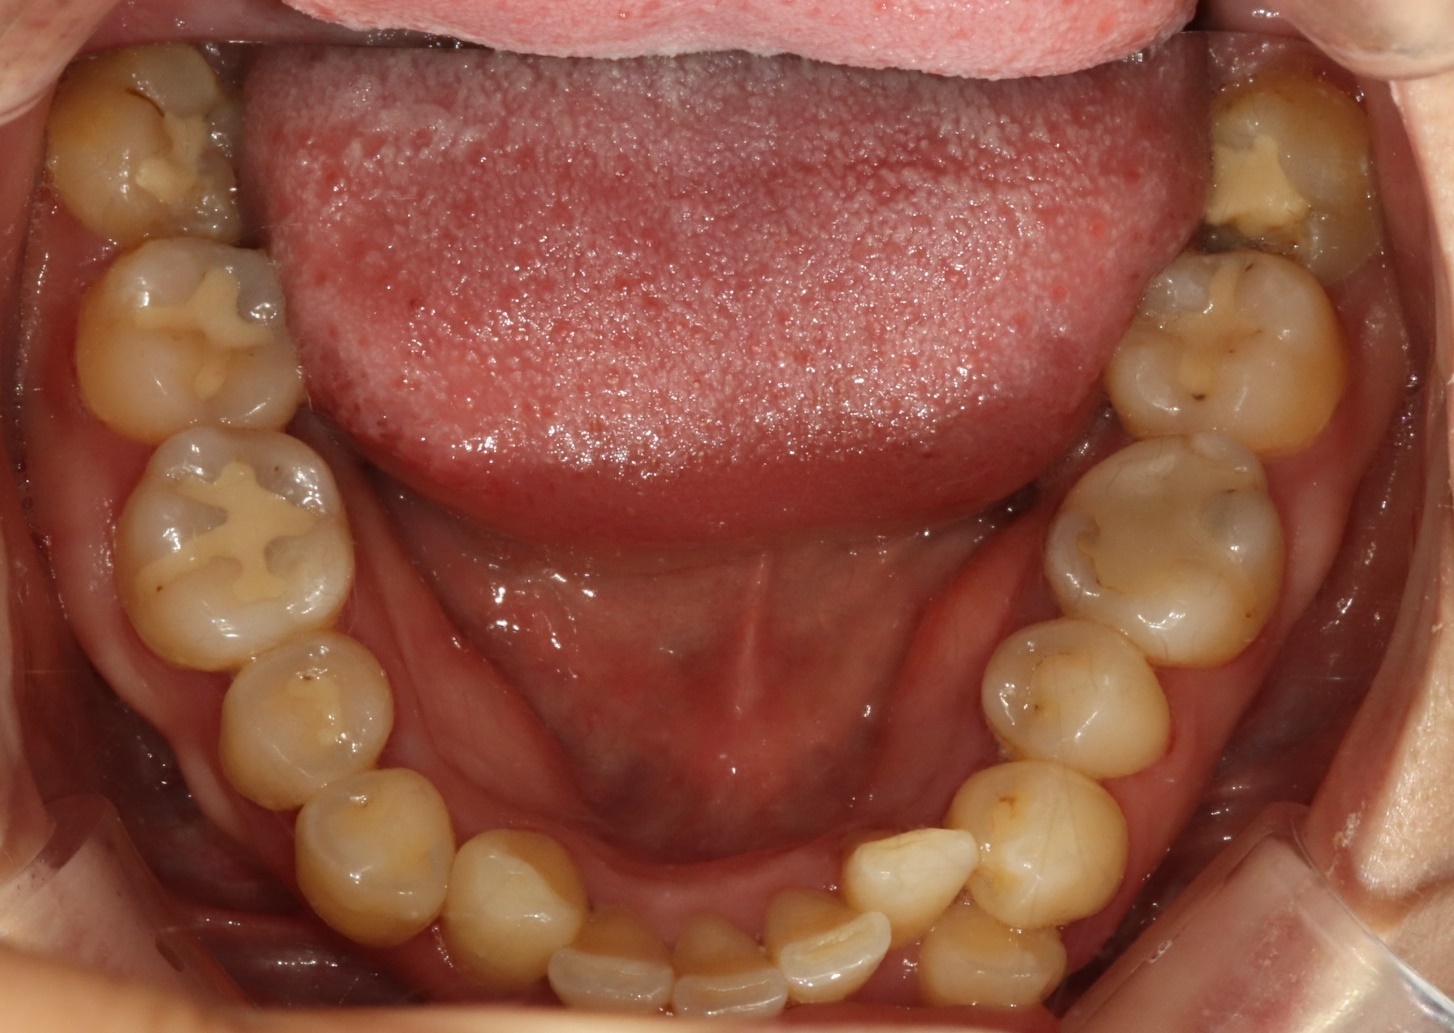

어금니 크라운

Before

After

대량 충치로 손상된 어금니 완전 복원